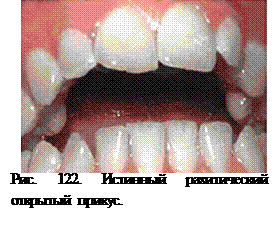

Рахит проявляется формированием истинного открытого (рахитического) прикуса (в отличие от ложного - травматического) (рис. 122).

Истинным называется открытый прикус, возникший у детей перенесших рахит.